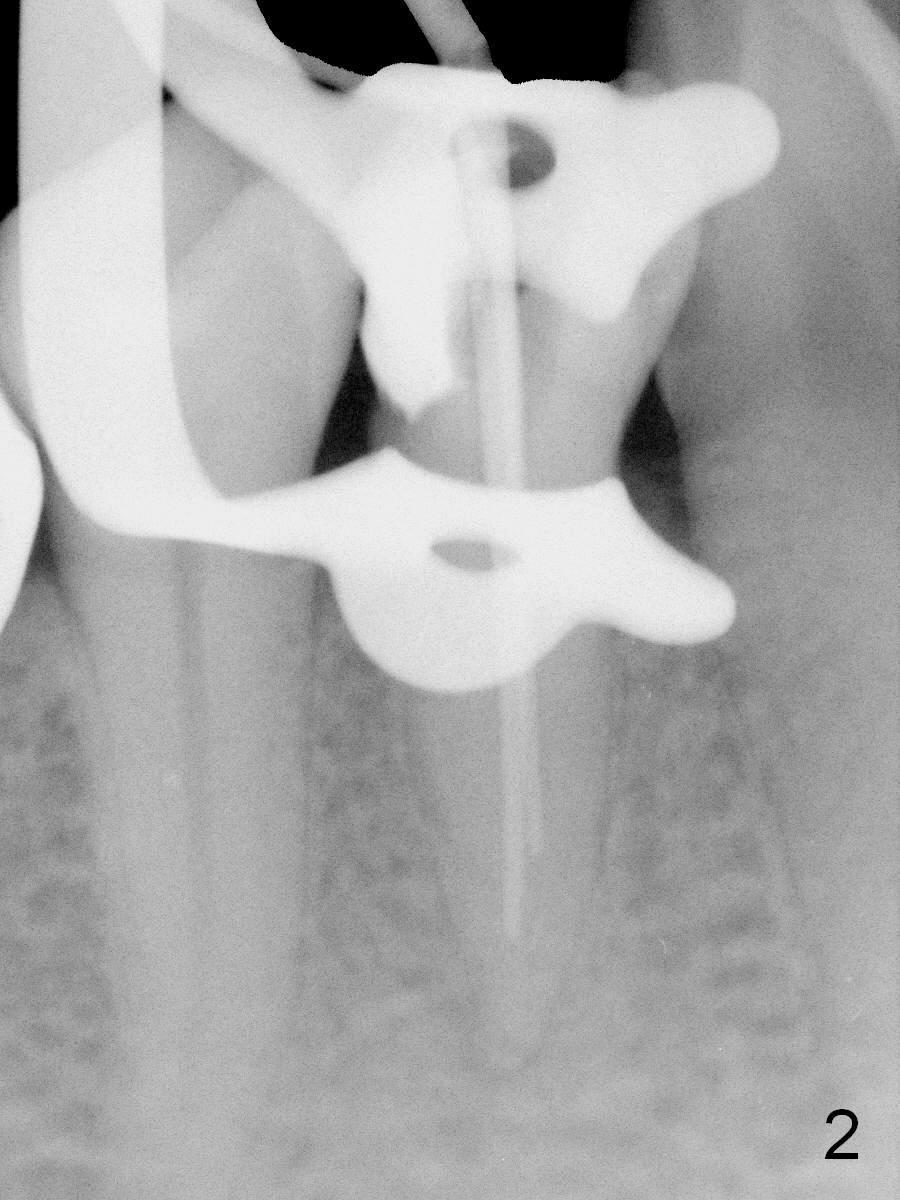

Further exploration finds a lingual canal (Fig.2), which is debrided until 30 hand file. When the canals are being filled with gutta percha and paste, the lingual canal is not filled (Fig.2). After removal of buccal gutta percha, the lingual canal is enlarged with 30/.04 rotary file and filled (Fig.4). The lingual canal is laterally condensed; composite build up is finished (Fig.5).

In fact CBCT has ben taken for #14 RCT and is reviewed prior to this case. If CT were reviewed, finding the extra canal would be easier (Fig.6 coronal section). It appears that the apical canals are blocked (Fig.7). The canal is split at the middle of the root, as shown in Fig.8,8' (axial upper section, as shown by the upper dashed line in Fig.6) and in Fig.9,9' (axial lower section, as shown by the lower dashed line in Fig.6). The buccal canal should not have been debrided with 40/.04 rotary file (30/.04 would have been better). In all, the tooth has two fused roots (Fig.3,9,9').